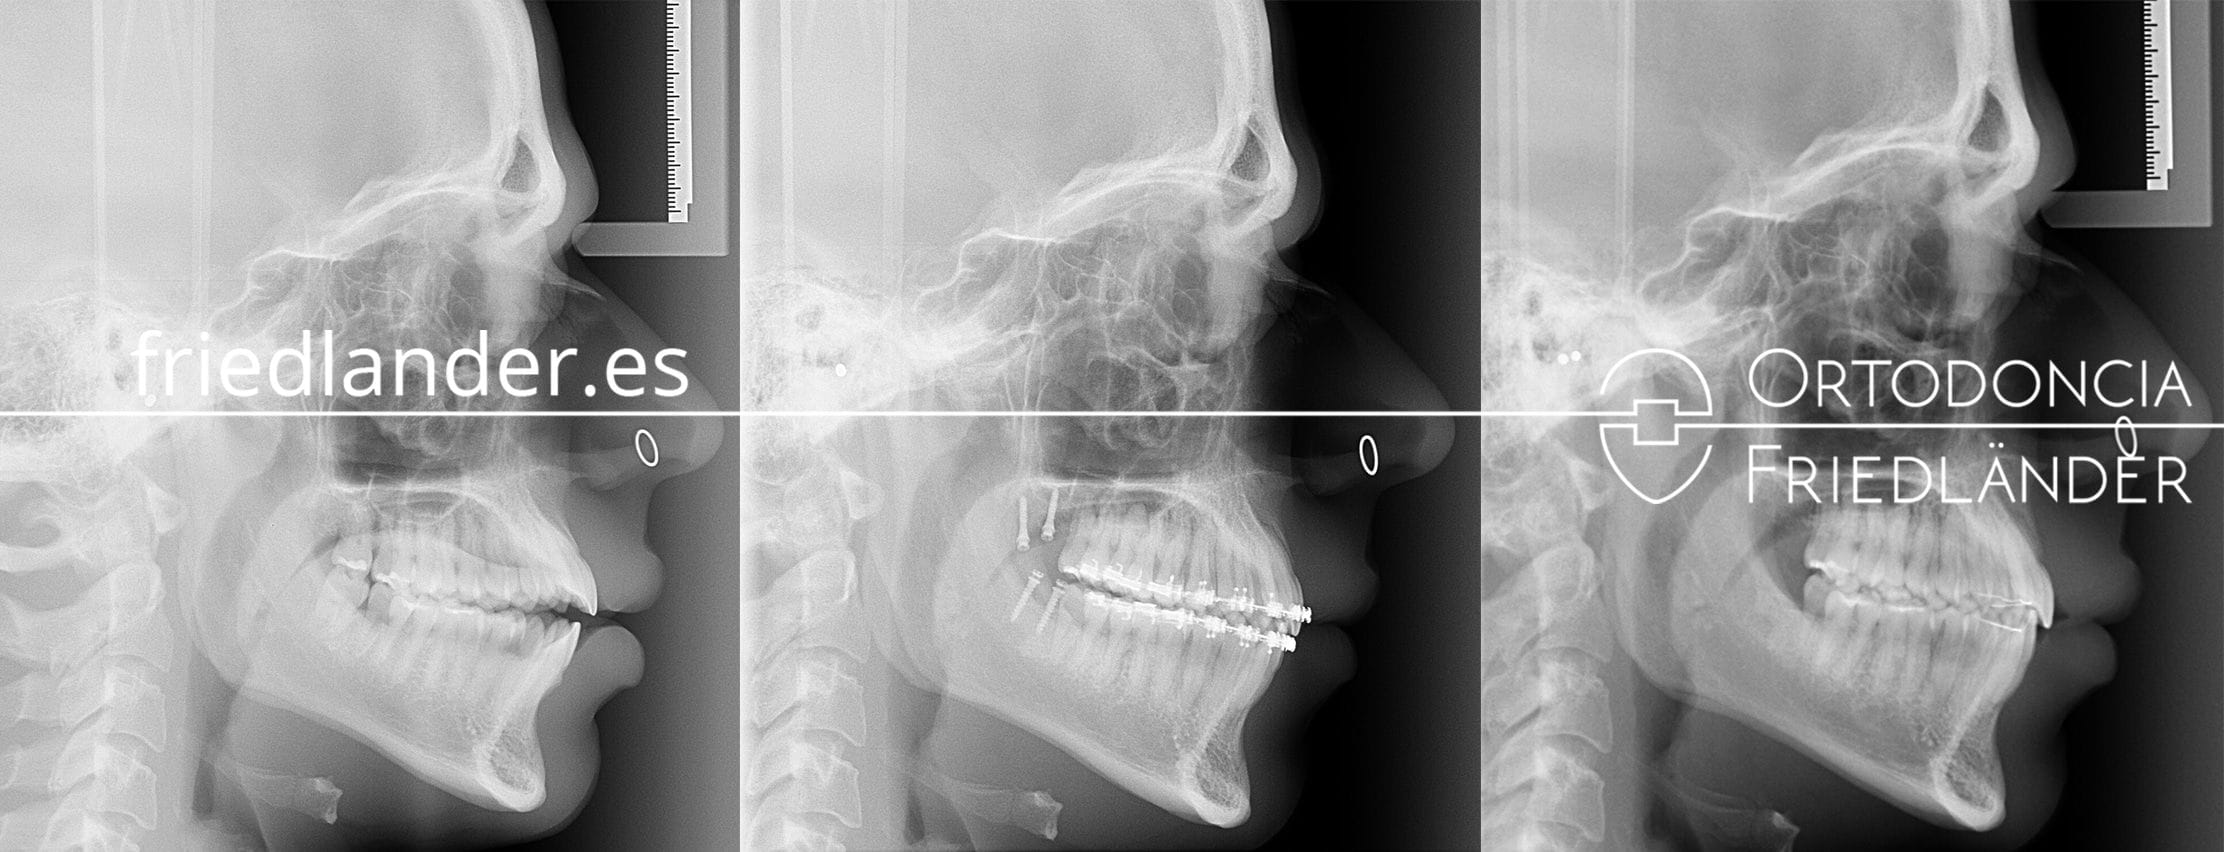

En la siguiente radiografía lateral inicial se puede observar la mordida abierta de unos 3mm (izquierda), en la radiografía lateral final (derecha) se puede observar una sobremordida de 3mm, es decir, hemos conseguido unos 6mm de movimiento vertical a nivel de los incisivos.

Radiografias laterales de antes durante y después del tratamiento.